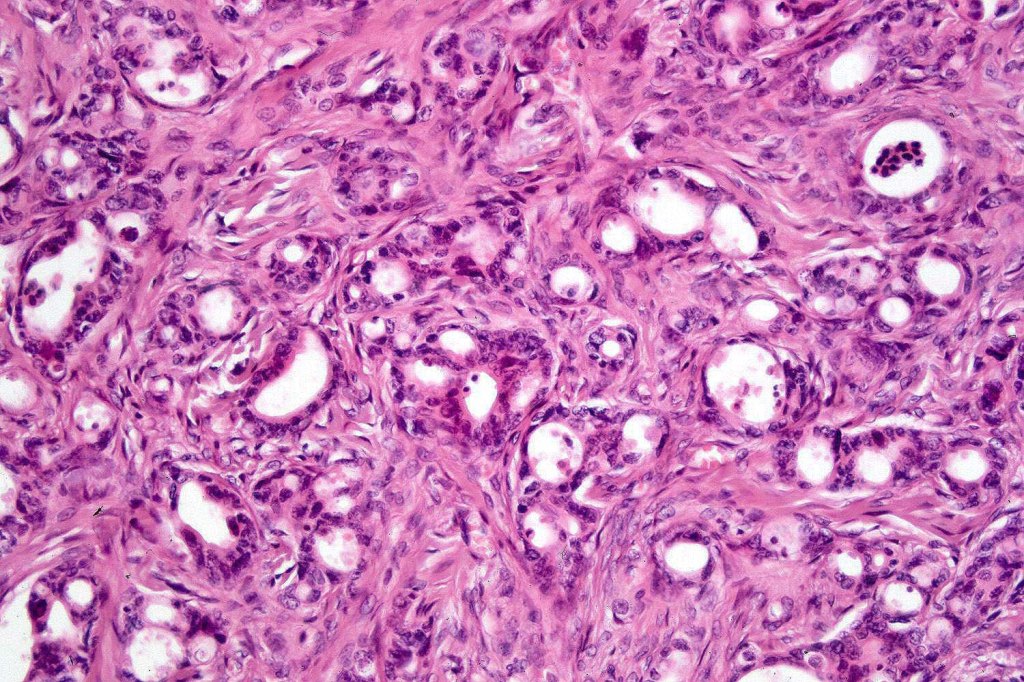

Histological features

Dermal tumor +/- subcutaneous fat

•Nests & cords of epithelial cells showing ductal differentiation/intracytoplasmic lumina embedded in a dense fibrous stroma

•Eosinophilic cytoplasm & irregular vesicular nuclei with small nucleoli

•Variable pleomorphism & mitoses

•Perineural infiltration & lymphovascular invasion commonly present